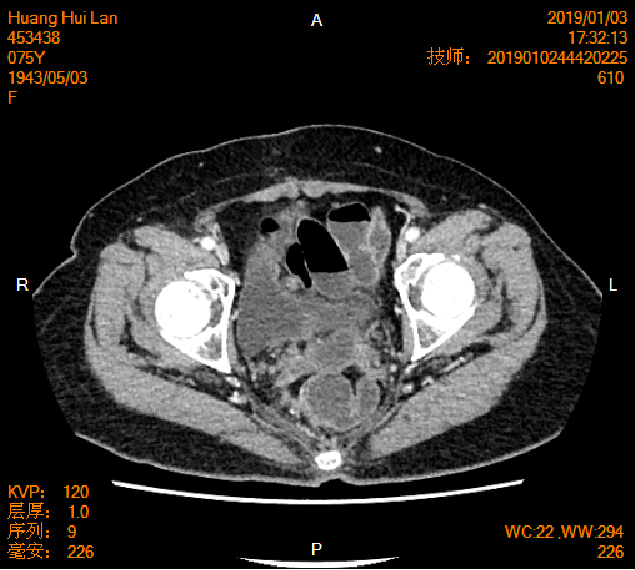

2016-04-13胸腹盆CT

2016-4-22行剖腹探查术+全子宫及双附件切除术+大网膜切除术+Dixons术(骶前保肛直肠癌根治术)

(盆腔肿物)约15X10X3cm,切面灰白,质脆,镜下:可见卵巢结构,其内见腺癌浸润。免疫组化:癌细胞CK20(+),CK(+),CDX-2(+),M-CEA(+),Villin(+),TTF-1(-),CK7(-)。符合直肠腺癌卵巢转移。

直肠中分化腺癌双肺卵巢转移 RAS突变 pT4aN1aM1b

2019-01-04胸腹盆CT